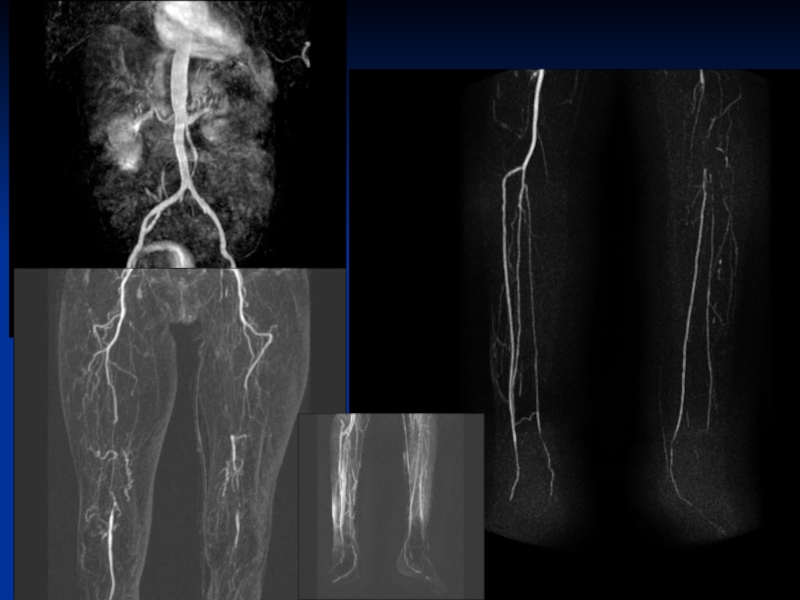

Слайд 57Обструктивное заболевание периферических сосудов

Снижение дозы КВ

Нет потери

информации (право/лево)

Высокое пространственное разрешение

Высокое качество изображений

Dr. J.

Barkhausen, University Clinic of Essen, Germany; MAGNETOM Avanto

Обструктивное заболевание периферических сосудов Снижение дозы КВ Нет потери информации (право/лево) Высокое пространственное разрешение Высокое качество изображенийDr.